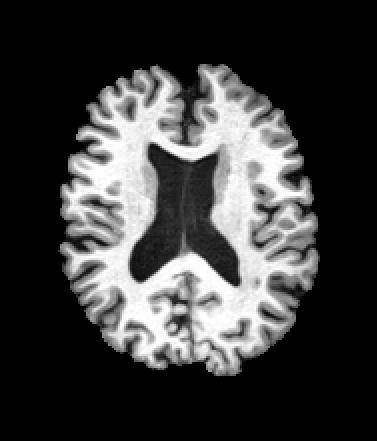

A trained MetaVoxel model can be unconditionally sampled by drawing Gaussian or categorical noise for each variable at timestep , and iteratively apply the denoising network until reaching . Unlike conventional diffusion models that focus solely on image generation, MetaVoxel can generate coherent synthetic patient profiles from the joint distribution , as shown in Figure 2.

| Age: 64.0 | Age: 53.8 | Age: 70.9 | Age: 76.9 |

| Sex: Male | Sex: Female | Sex: Female | Sex: Male |

![]() |

| Age: 80.9 | Age: 77.7 | Age: 73.2 | Age: 84.6 |

| Sex: Male | Sex: Female | Sex: Female | Sex: Female |